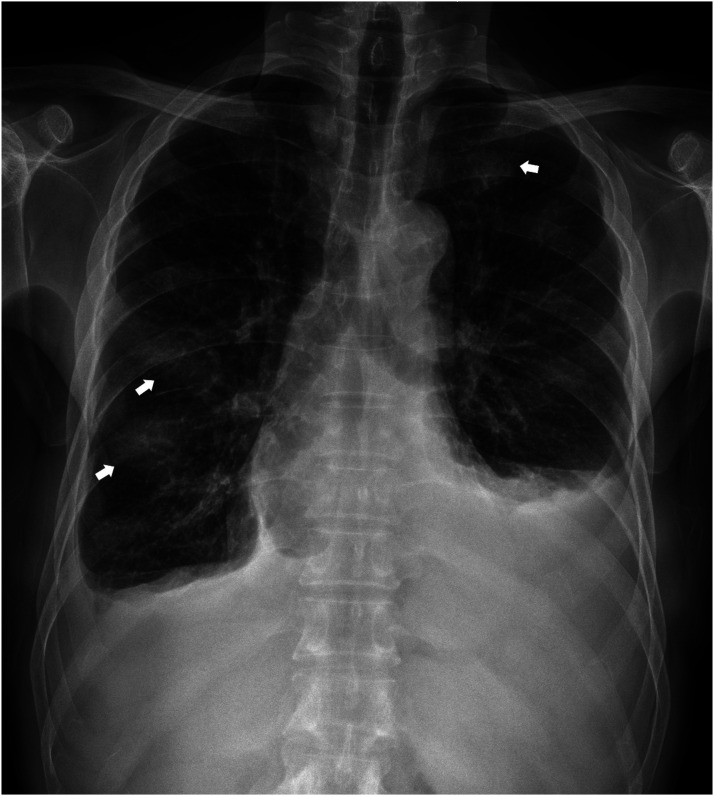

Extramedullary involvement of multiple myeloma is an uncommon and aggressive condition characterized by proliferation of monoclonal plasma cells located outside the bone marrow. This report describes the imaging findings of a patient who presented with continuous soft-tissue disease on the ribs, suspected as extrapleural space tumors on chest CT. The patient was diagnosed with multiple myeloma through surgical biopsy of the tumor and bone marrow.